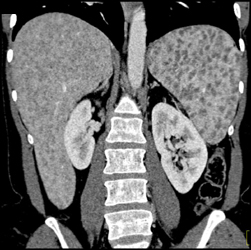

Splenic Artery Aneurysm